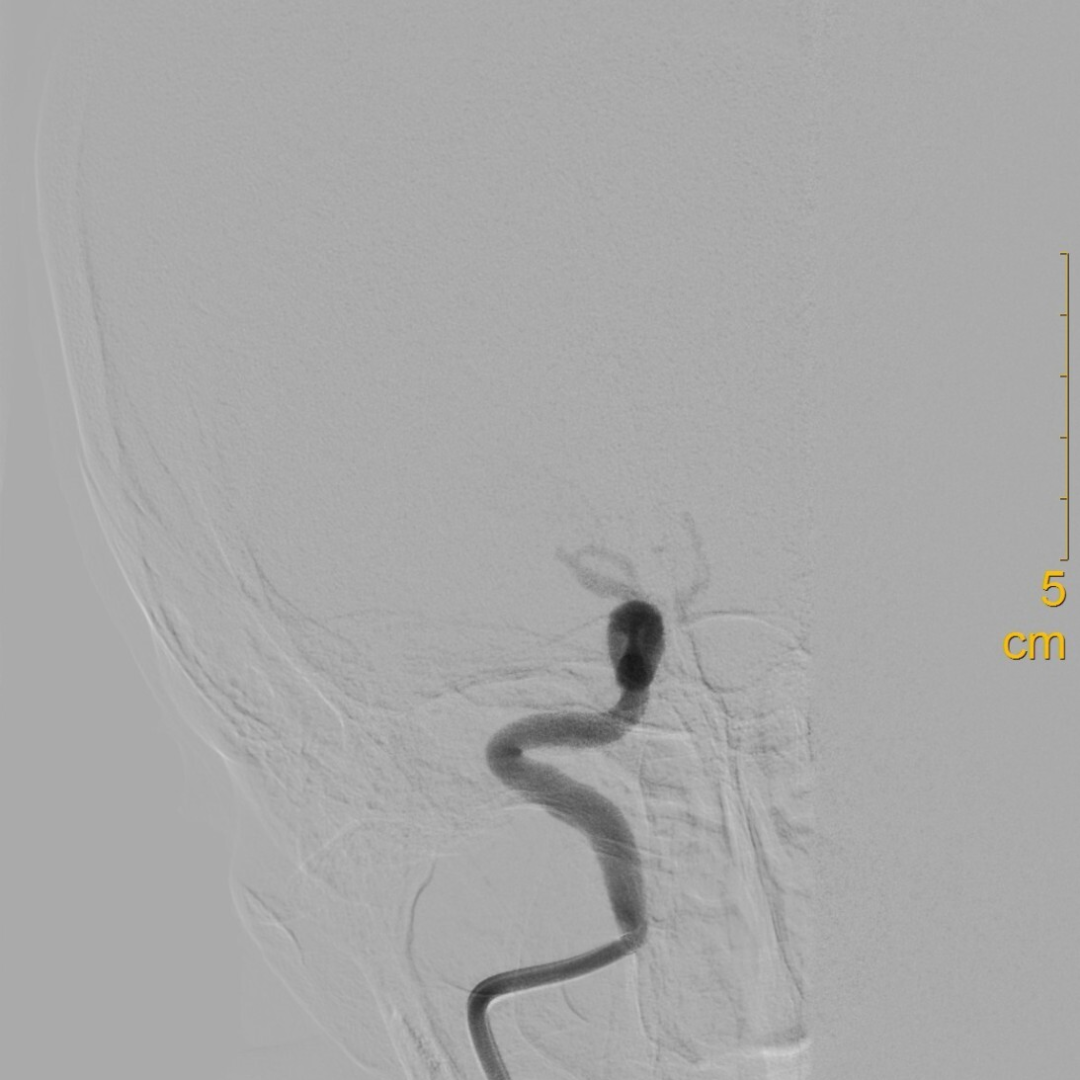

术前影像

1年前的MRA提示该部位重度狭窄。